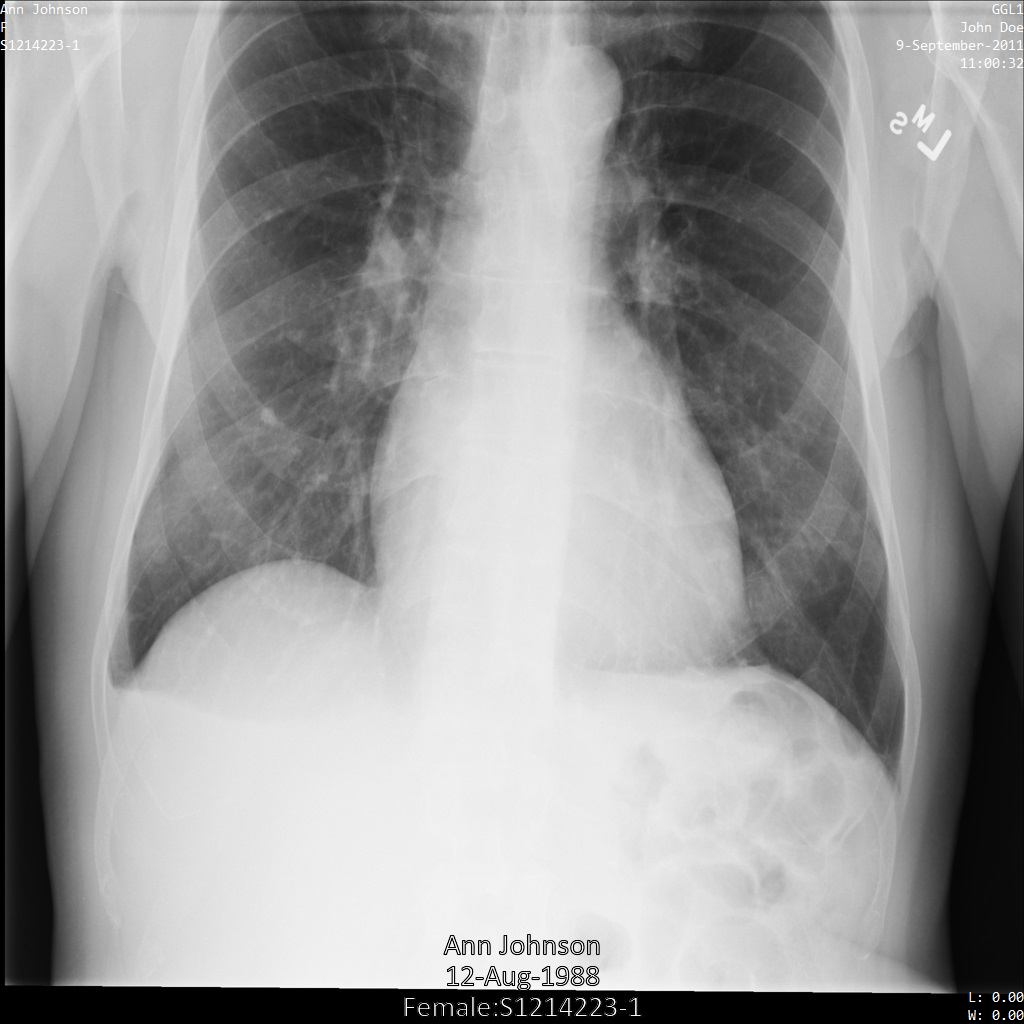

Contoh dalam panduan ini menggunakan satu instance DICOM, tetapi Anda juga dapat menghilangkan identitas beberapa instance.

Setiap bagian berikut memberikan contoh cara melakukan de-identifikasi data DICOM menggunakan berbagai metode. Output gambar yang tidak diidentifikasi disediakan dengan setiap sampel. Setiap sampel menggunakan gambar asli berikut sebagai input:

Anda dapat membandingkan gambar output dari setiap operasi penghapusan identitas dengan gambar asli ini untuk melihat efek operasi.

Setelah mengirimkan gambar ke Cloud Healthcare API menggunakan

profil filter tag ATTRIBUTE_CONFIDENTIALITY_BASIC_PROFILE, gambar akan muncul

seperti berikut. Meskipun metadata yang ditampilkan di sudut atas gambar telah disamarkan, PHI yang tercetak di bagian bawah gambar tetap ada.

Untuk menghapus teks sisipan juga, lihat

Menyamarkan teks sisipan dari gambar.